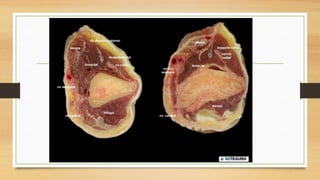

ANATOMIA

QUIRURGICA

• CAMBIO DE FORMA EN EL

HUMERO A MEDIDA QUE SE

HACE MAS DISTAL